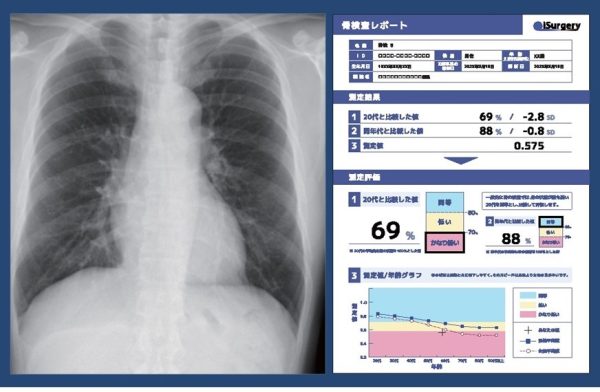

本実証実験では、iSurgeryのAI医療機器「医用画像解析ソフトウェア Chest Bone Indicator」(注5)(以下、AI医療機器)を活用し、富士通グループの従業員向け健康診断の受診者に対して、胸部X線写真から骨の状態を評価し、結果を通知する。評価結果に応じて専門医、精密検査の受診を勧奨するほか、評価結果にかかわらず東京慈恵会医科大学が提供する骨の健康に関する基礎知識を活用して、予防のための健康指導なども行う。

iSurgeryが提供するAI医療機器は、企業の法定検査項目である胸部X線検査で撮影した写真を活用することで、骨密度測定の追加検査なしに骨の状態の評価が可能であることから、今般、共同で実証実験に取り組むこととした。

注4 骨評価:深層学習による画像解析技術を応用し、胸部X線写真から骨の状態を解析、若年平均値や同年代と比較し、骨粗しょう症の早期発見につなげる。

注5 医用画像解析ソフトウェア Chest Bone Indicator:胸部X線画像を深層学習によって画像解析し、骨の状態を解析するiSurgeryが開発したソフトウェア。追加の検査時間・労力・被爆なしに骨の状態の検査が可能。X線撮影装置があればどこでも導入可能、既存の医療用画像管理システム画面からワンクリックで解析完了できる。場所、人、時間を費やさずに、大幅に検査を増やすことができる。2023年4月18日に薬事認可(医療機器認証番号:305ADBZX00032000)済。